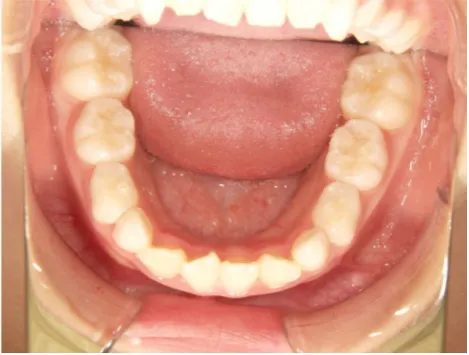

治療前①小2:8y1m 初診